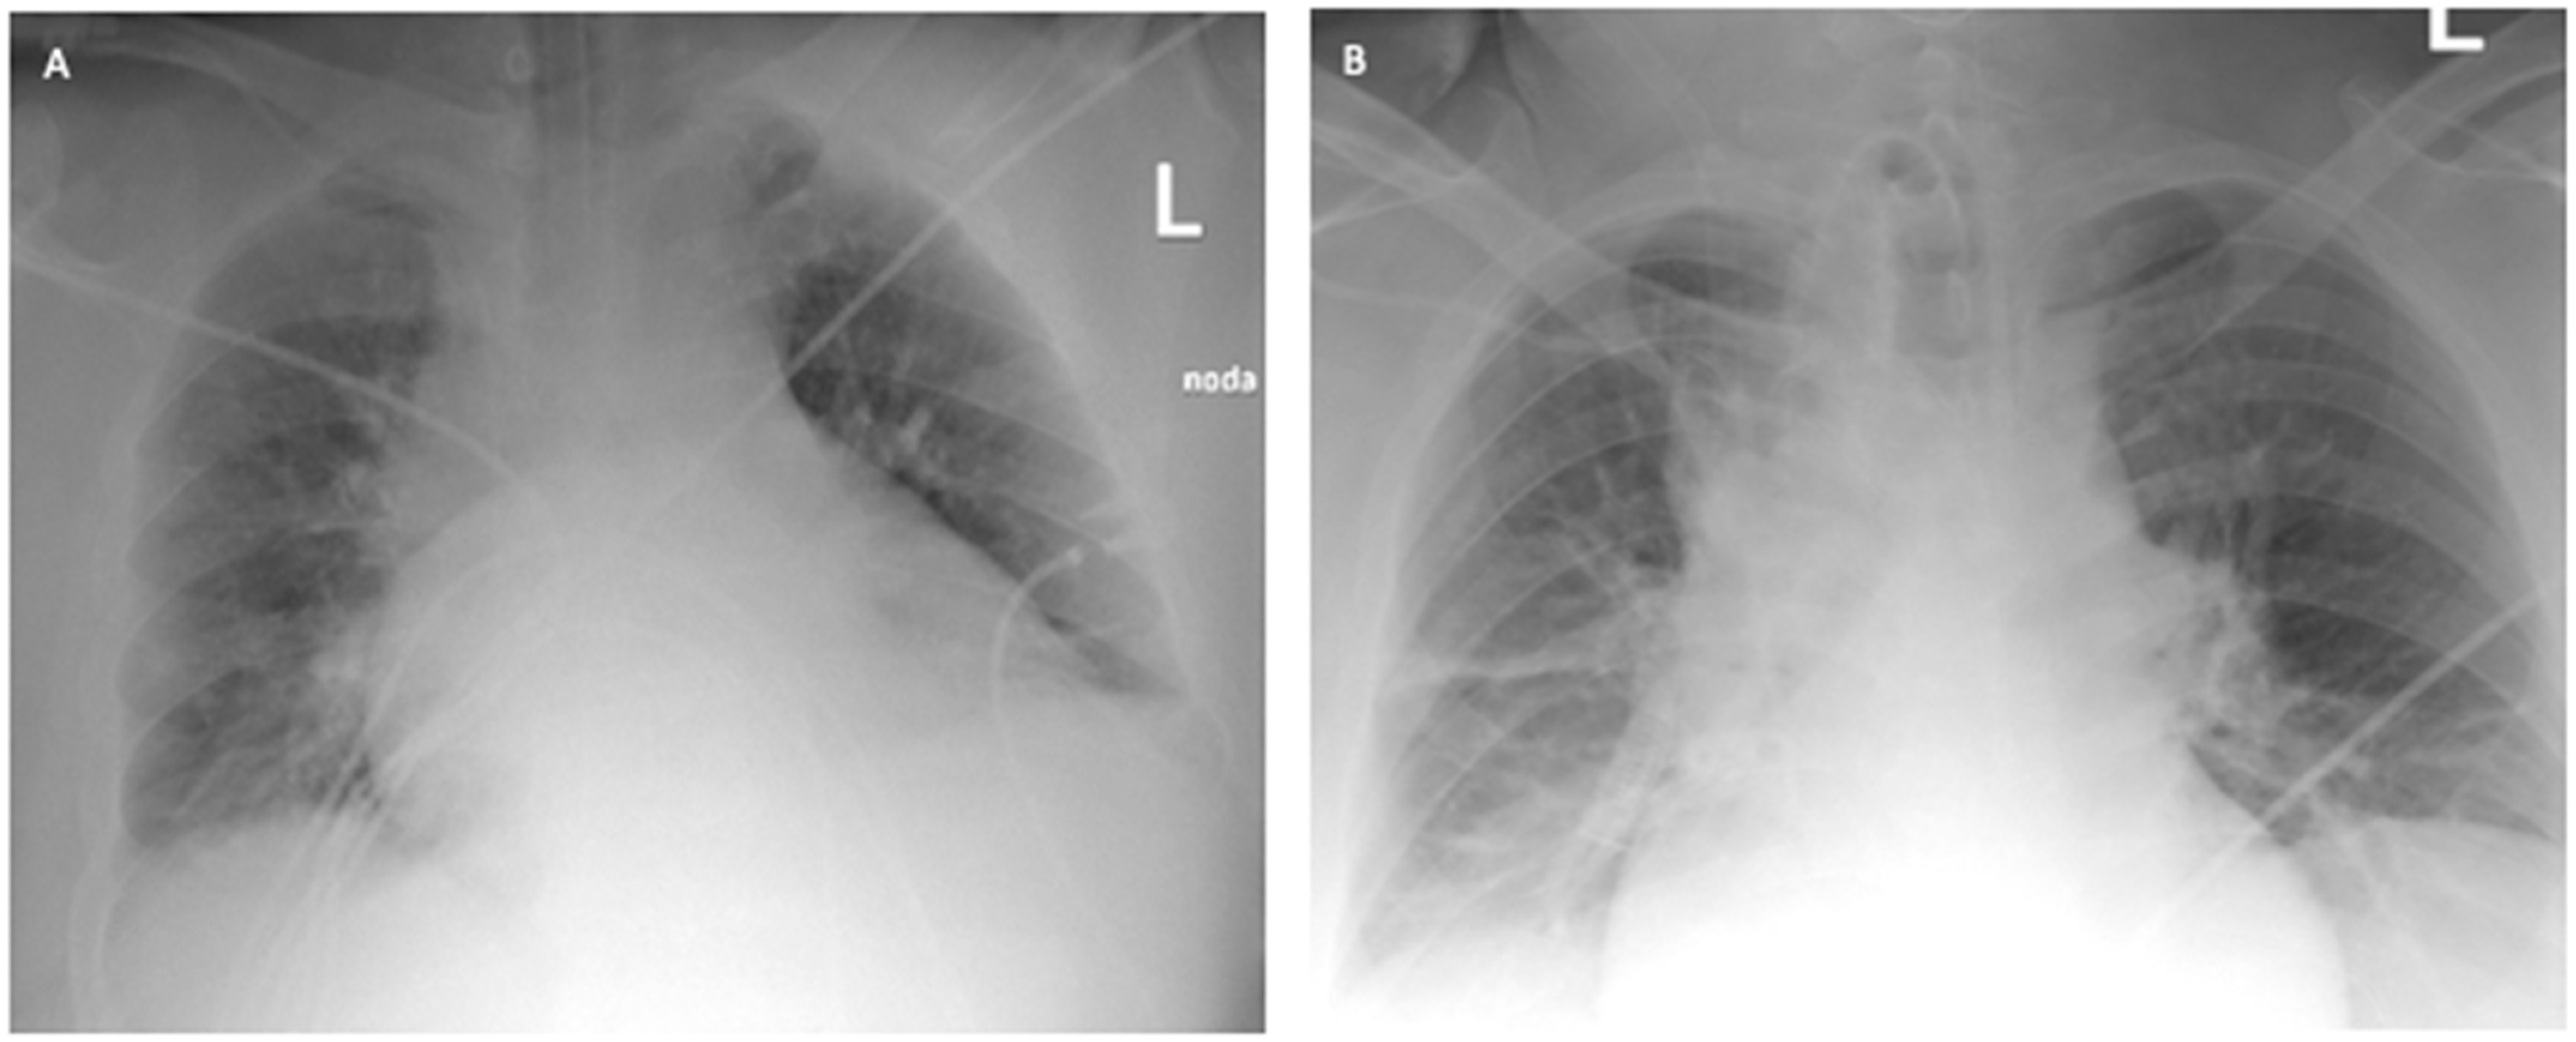

A 41-year-old obese man with a BMI of 44.5 kg/m2 (class III obesity) was admitted to the ICU on day 2 after admission to the hospital due to respiratory failure in the course of SARS-CoV-2 infection. The patient had comorbidities: type 2 diabetes mellitus and obstructive sleep apnea. On admission to the hospital, a CT scan of the lungs showed lesions typical of COVID-19 (Figure 3).

Figure 3. ICU: (A) upper lung segments; (B) middle lung segments; (C) basal lung segments (Case 2).